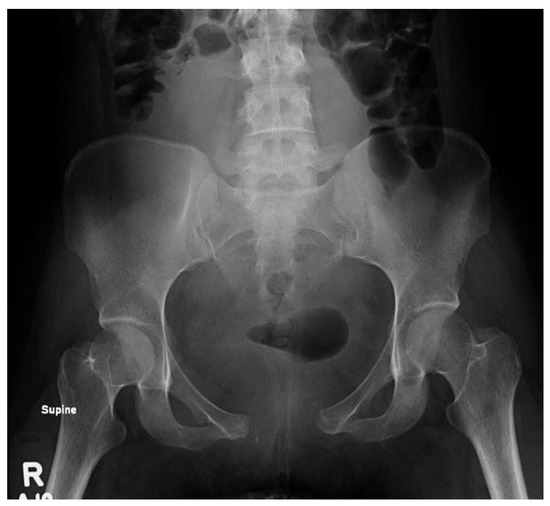

Radiographs were obtained, revealing a 5.0 cm separation of the pubic symphysis and anterior widening of the sacroiliac joint (Figure 1). A pelvic binder was placed to provisionally stabilize the pelvis, and the patient was immediately transferred to a higher level of care for evaluation and management.

Figure 1. Initial AP pelvis radiograph on presentation demonstrating a 5.0 cm separation of the pubic symphysis and anterior widening of the sacroiliac joint.